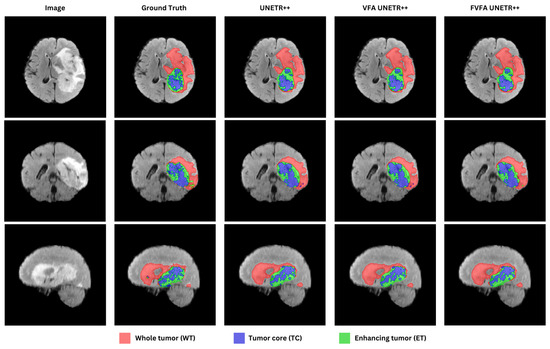

UNETR++ with Voxel-Focused Attention: Efficient 3D Medical Image Segmentation with Linear-Complexity Transformers

by Sithembiso Ntanzi and Serestina Viriri

Appl. Sci. 2025, 15(20), 11034; https://doi.org/10.3390/app152011034 - 14 Oct 2025

There have been significant breakthroughs in developing models for segmenting 3D medical images, with many promising results attributed to the incorporation of Vision Transformers (ViT). However, the fundamental mechanism of transformers, known as self-attention, has quadratic complexity, which significantly increases computational requirements, especially [...] Read more.

There have been significant breakthroughs in developing models for segmenting 3D medical images, with many promising results attributed to the incorporation of Vision Transformers (ViT). However, the fundamental mechanism of transformers, known as self-attention, has quadratic complexity, which significantly increases computational requirements, especially in the case of 3D medical images. In this paper, we investigate the UNETR++ model and propose a voxel-focused attention mechanism inspired by TransNeXt pixel-focused attention. The core component of UNETR++ is the Efficient Paired Attention (EPA) block, which learns from two interdependent branches: spatial and channel attention. For spatial attention, we incorporated the voxel-focused attention mechanism, which has linear complexity with respect to input sequence length, rather than projecting the keys and values into lower dimensions. The deficiency of UNETR++ lies in its reliance on dimensionality reduction for spatial attention, which reduces efficiency but risks information loss. Our contribution is to replace this with a voxel-focused attention design that achieves linear complexity without low-dimensional projection, thereby reducing parameters while preserving representational power. This effectively reduces the model’s parameter count while maintaining competitive performance and inference speed. On the Synapse dataset, the enhanced UNETR++ model contains 21.42 M parameters, a 50% reduction from the original 42.96 M, while achieving a competitive Dice score of 86.72%. Full article